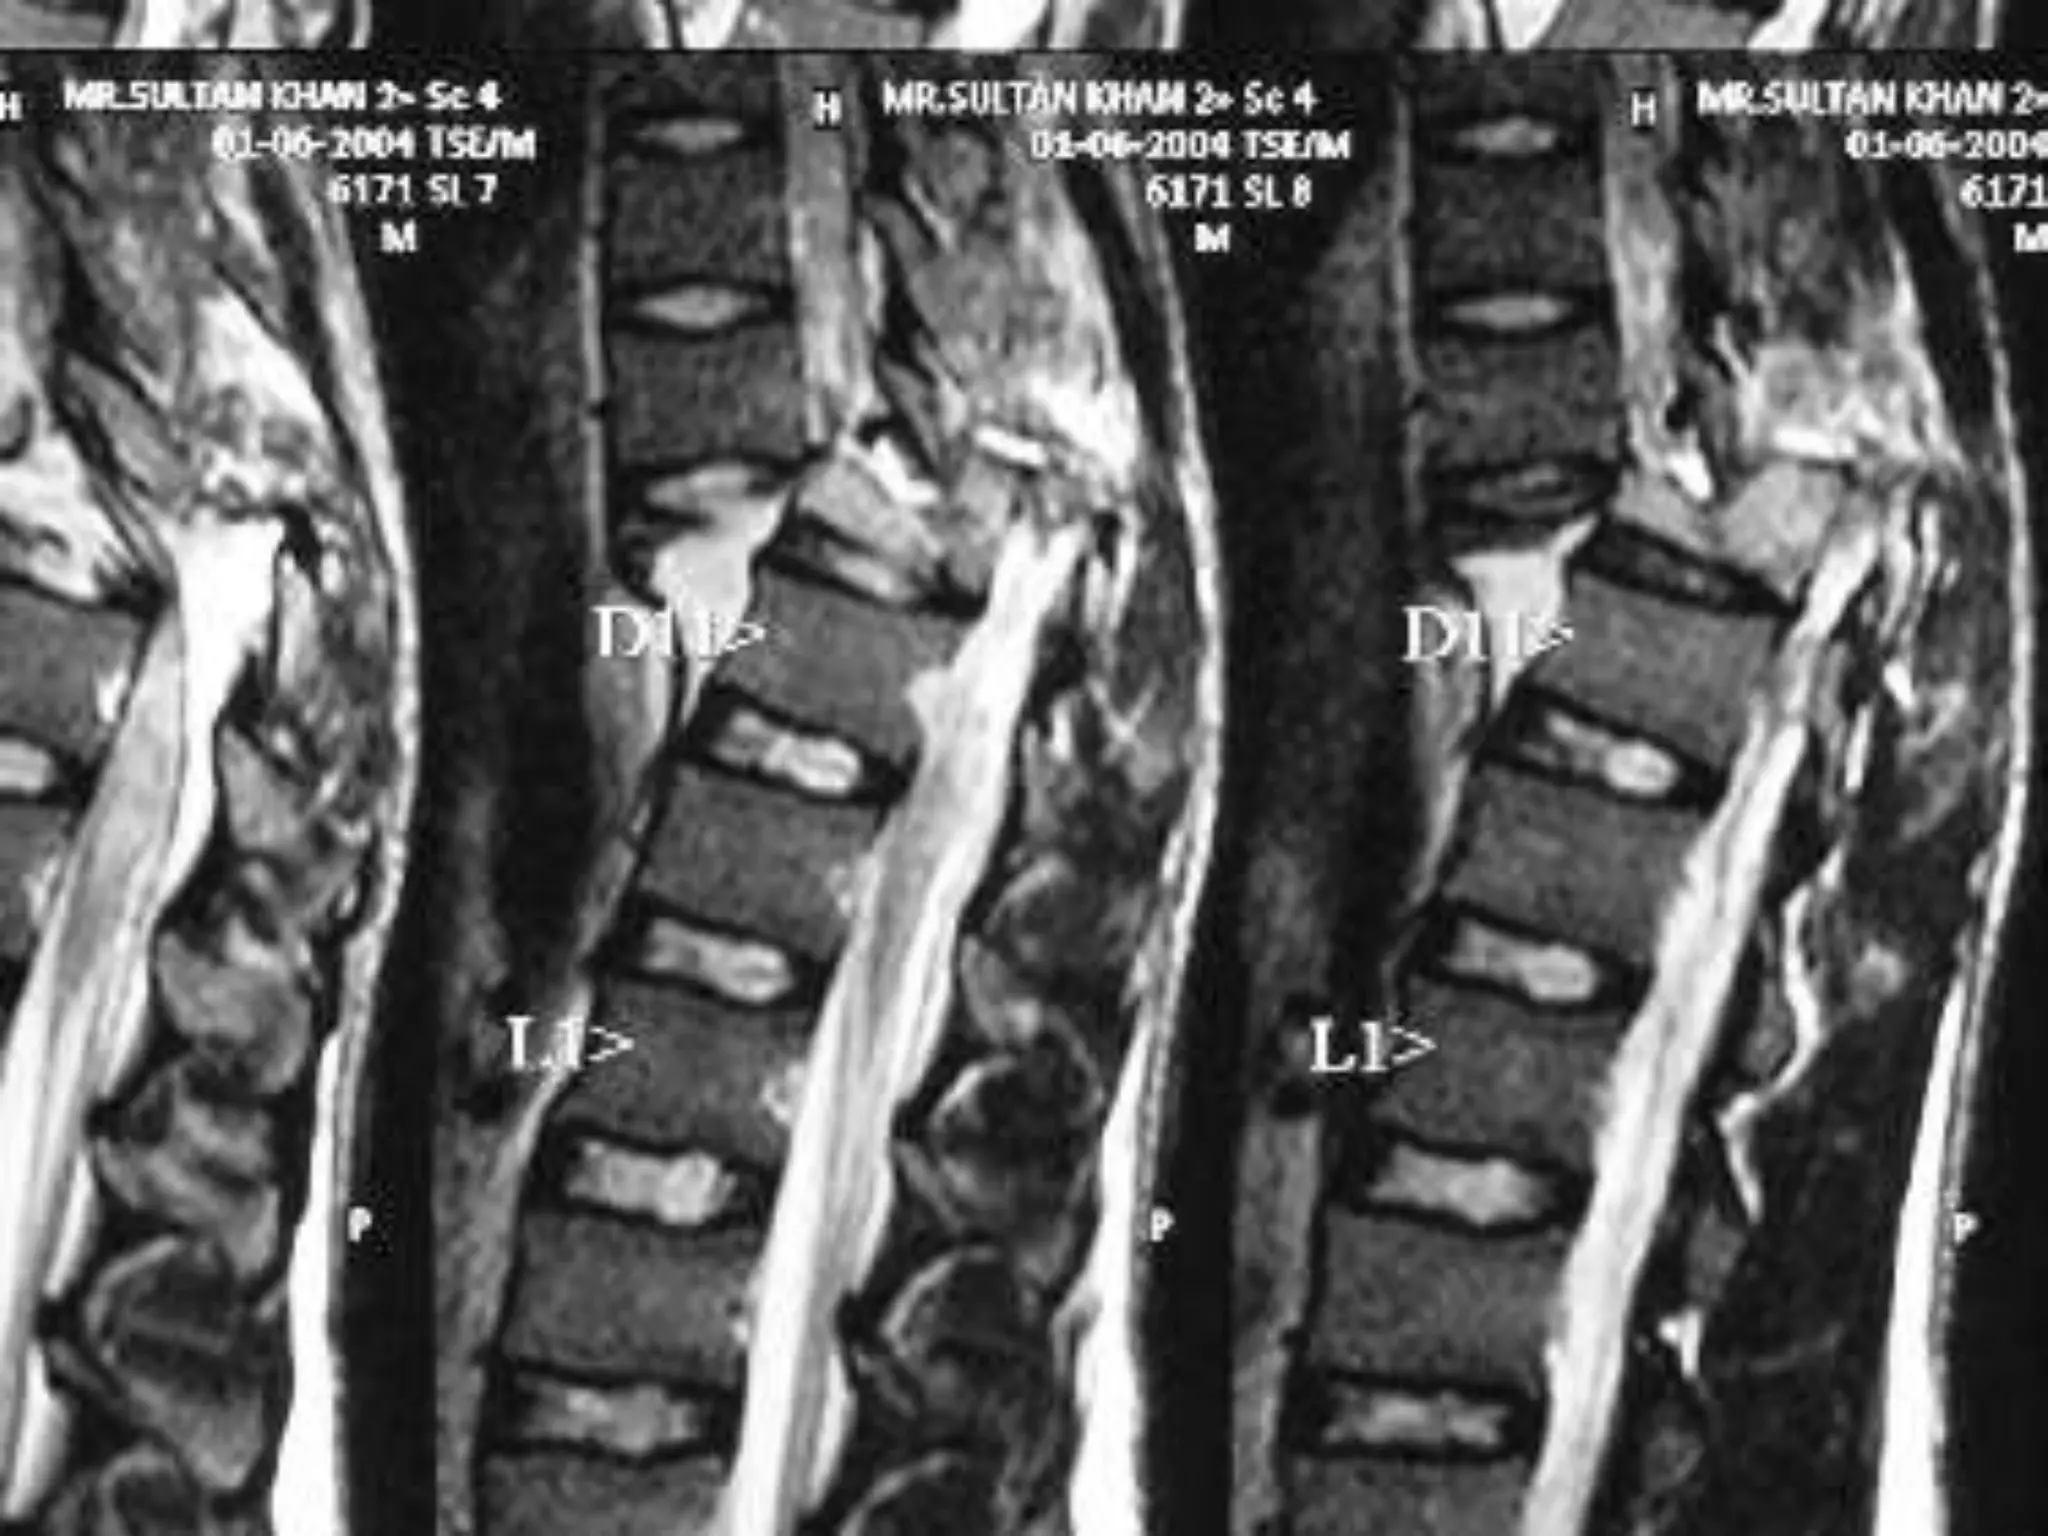

Disc at D12 – L1

Post operative Right sided Facetactomy